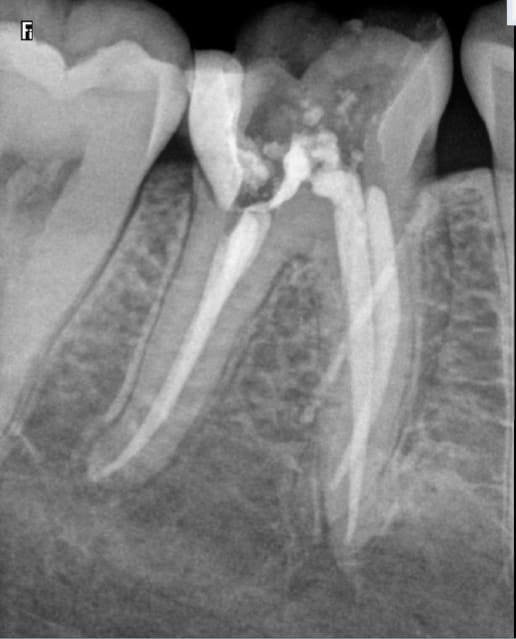

Sur la radio pré op ( avant anesthésie) on dirait qu'il y a un petit quelque chose sur la racine mésiale.

On dirait que l'image commençait déjà à apparaître sur la radio cone + pate non foulée.

Je visualise, peut être à tort, autour de la racine mésiale une pseudo image radioclaire.....